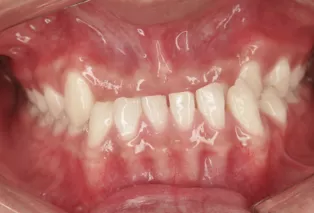

Intraoral photos